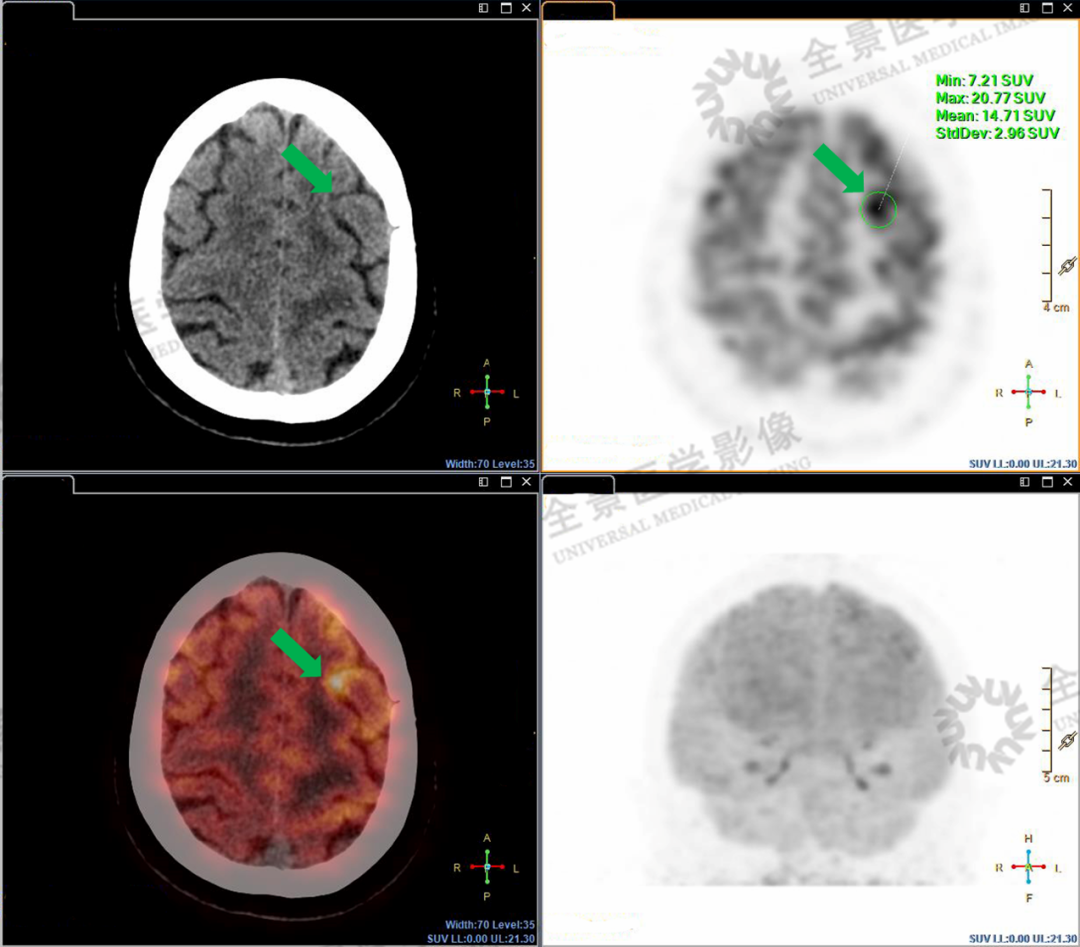

由于大脑皮层活跃时也有正常的代谢增高表现,仅凭PET/CT还不能准确定性脑部高代谢区域的性质,因此又有针对性地做了头颅磁共振扫描。

经过PET/CT和MR检查图像融合分析后确定:左额中回的高摄取区未发现占位,考虑为正常脑实质代谢;额定交界区高代谢结节考虑为转移。

额中回高代谢结节,考虑正常脑实质代谢